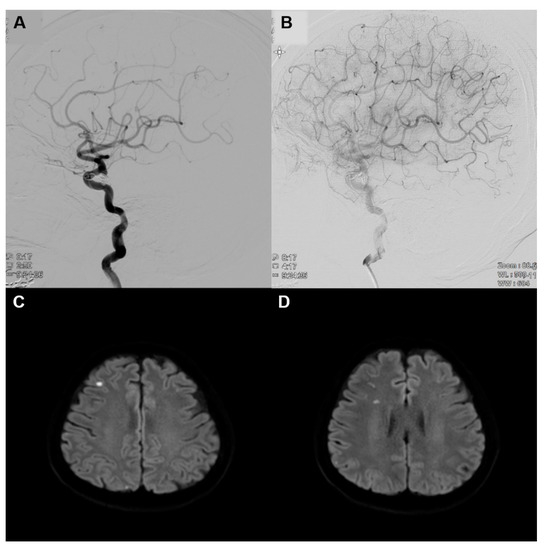

2. Case Presentation